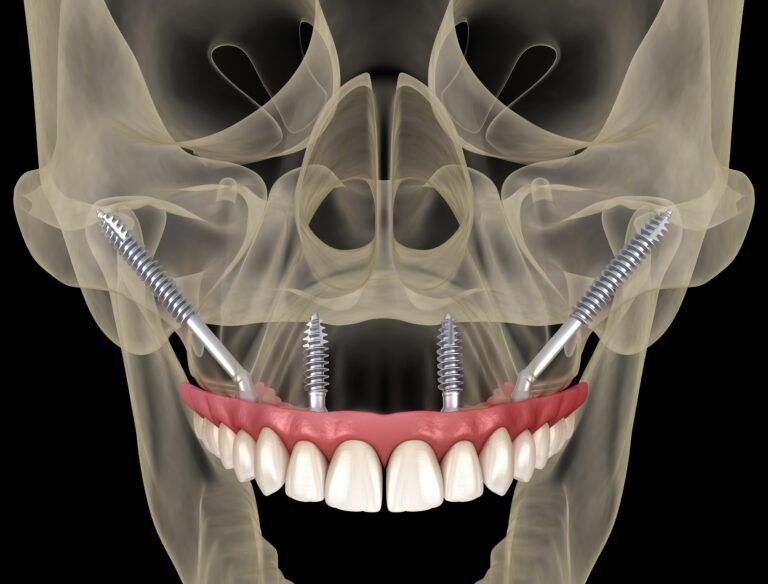

Implant-Supported Dentures Using Zygomatic Implants

In the realm of dental implants, innovative solutions continue to emerge, enhancing the quality of life for patients with severe tooth loss. Among these advancements, zygomatic implants stand out as a revolutionary option, particularly for those who have experienced significant

Zygomatic Implants: Advanced Solutions for Severe Bone Loss

Severe bone loss in the jaw can significantly impact an individual’s oral health, leading to challenges in dental restoration and affecting overall quality of life. Traditional dental implants often require a sufficient amount of bone for support, making them unsuitable